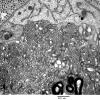

PERIPHERAL NEUROPATHY

4 AXONAL DEGENERATION

3 Electron Microscopy (3)